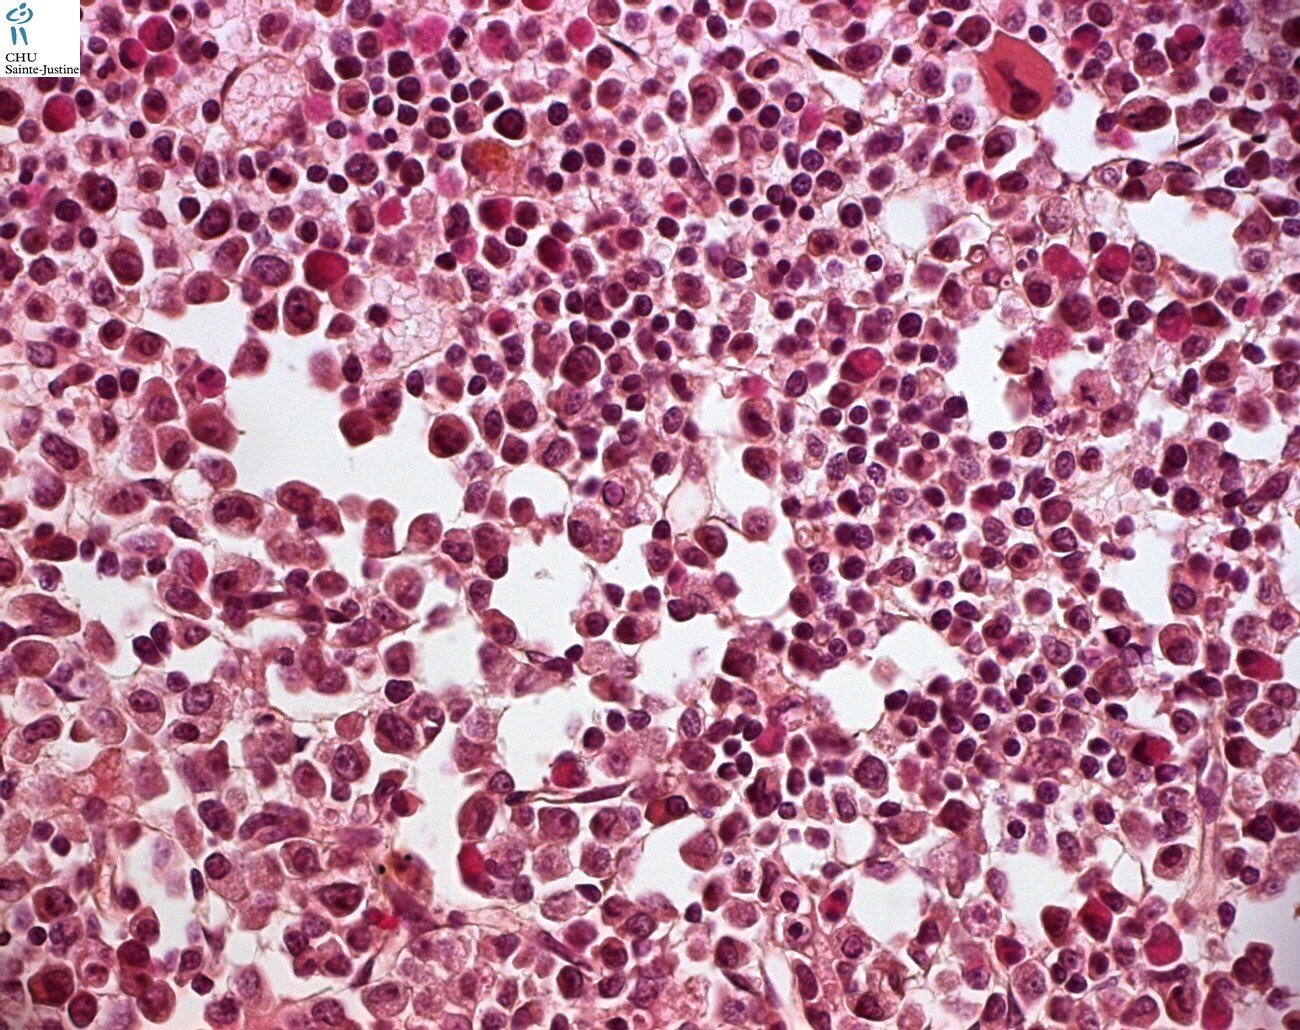

Morphology